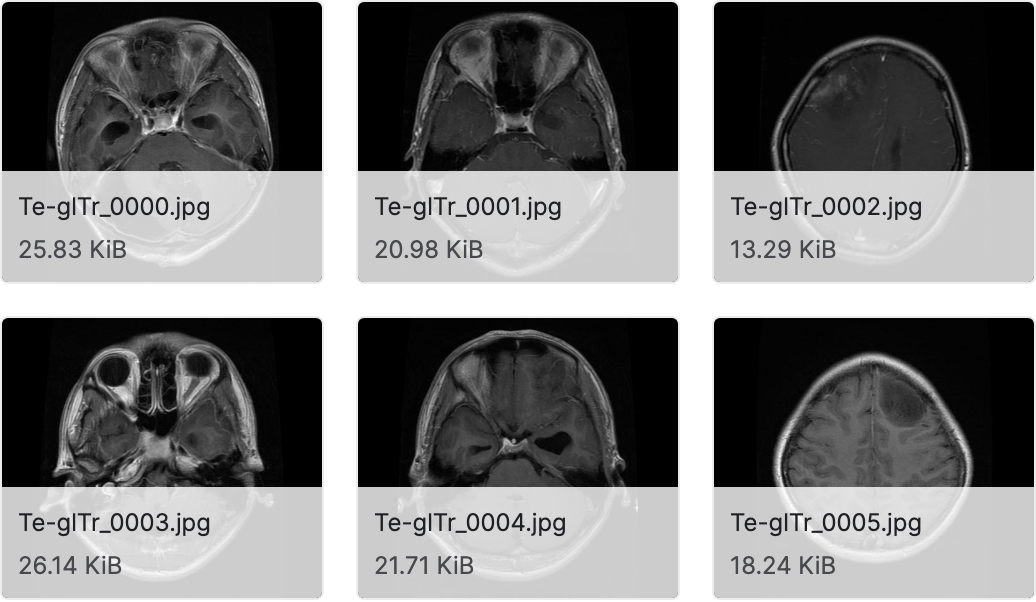

脑肿瘤 MRI 数据集

数据集下载地址:http://m6z.cn/63iHcV

该数据集包含7022张人脑 MRI 图像,分为 4 类:胶质瘤-脑膜瘤-无肿瘤和垂体。注意这个数据集中的图像大小是不同的。您可以在预处理并去除多余的边距后将图像调整为所需的大小。